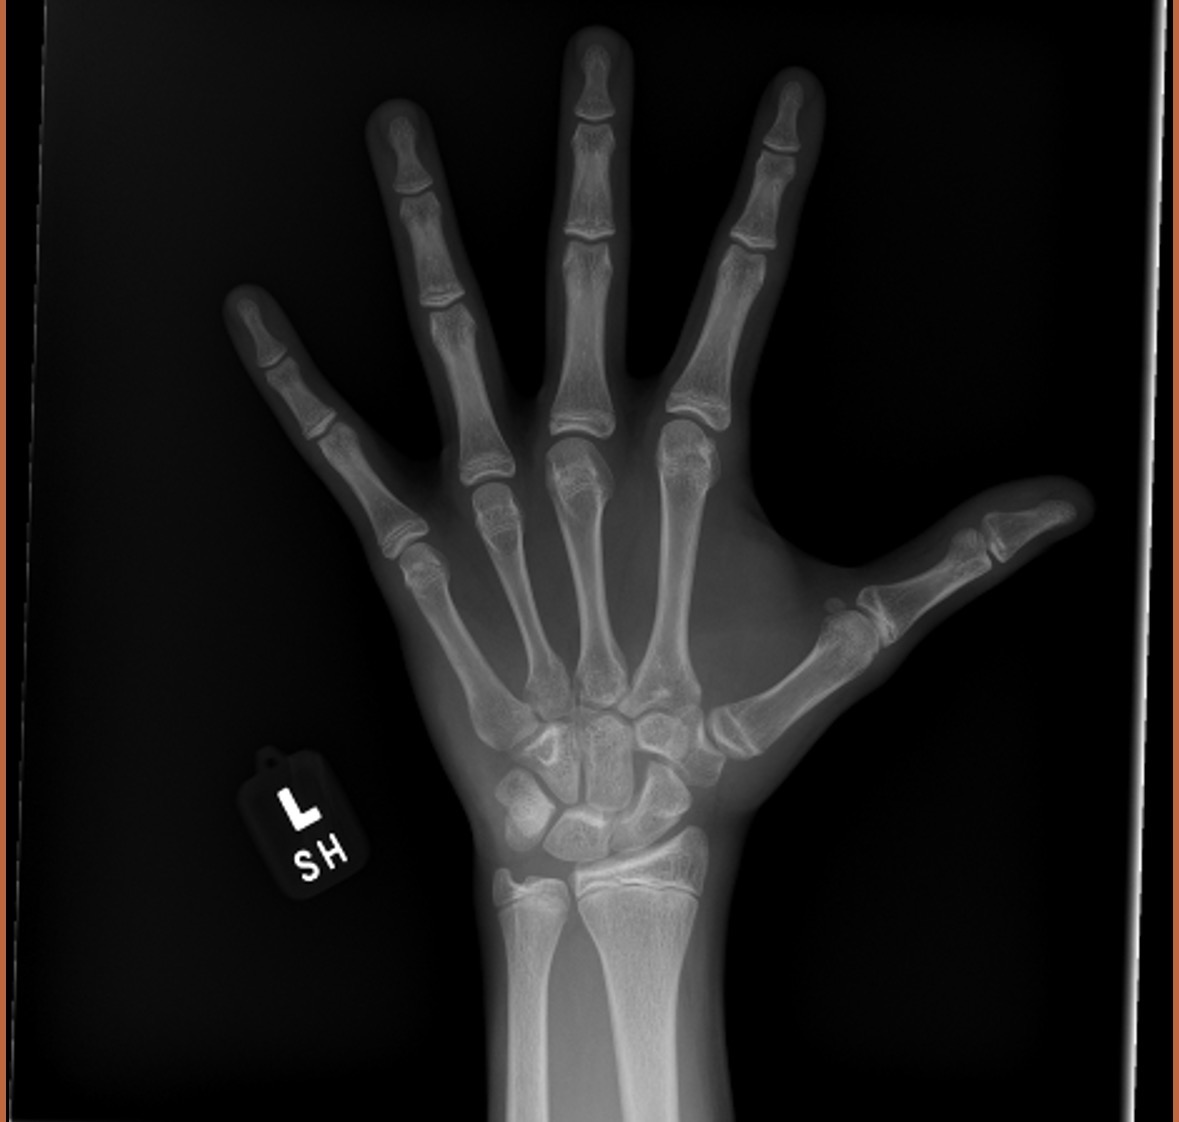

Bone age scan

How much time do i have left to grow

Well your plates are still pretty open so you'll probably be fine.

Still a good couple of inches left, maybe more.